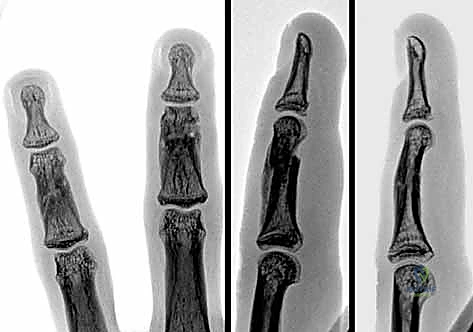

- التصوير بالأشعة السينية (X-rays): هو المعيار الذهبي لتشخيص كسور السلاميات. يطلب الدكتور هطيف دائماً ثلاث وضعيات أساسية:

- الأمامية الخلفية (AP View).

- الجانبية الحقيقية (True Lateral View): وهي الأهم لتقييم مقدار الانزياح الزاوي.

- المائلة (Oblique View): تساعد في رؤية الكسور الشعرية الدقيقة أو الكسور المفصلية الخفية.